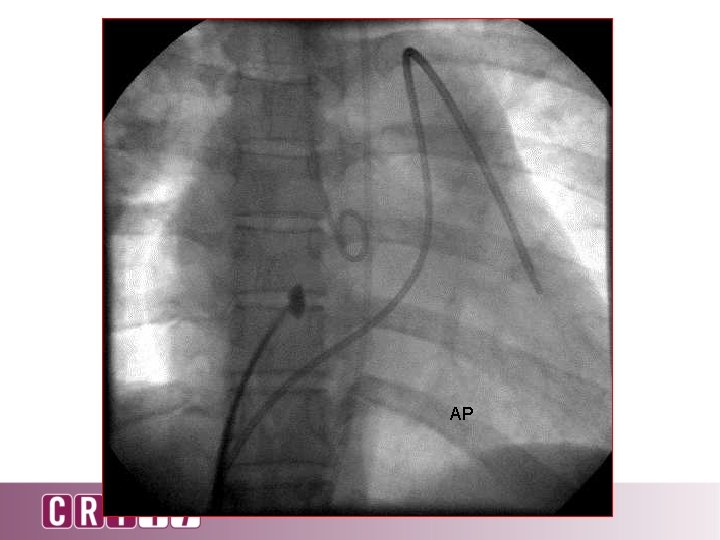

AP